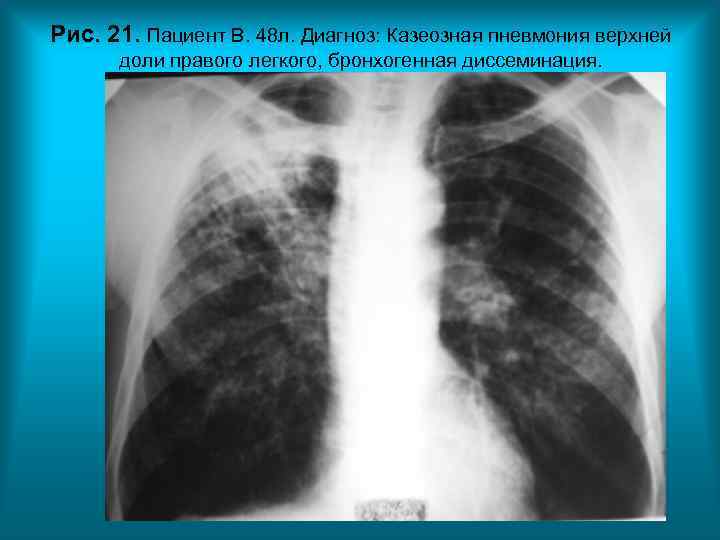

Рис. 21. Пациент В. 48 л. Диагноз: Казеозная пневмония верхней доли правого легкого, бронхогенная диссеминация. Н. С. Воротынцева. С. С. Гол